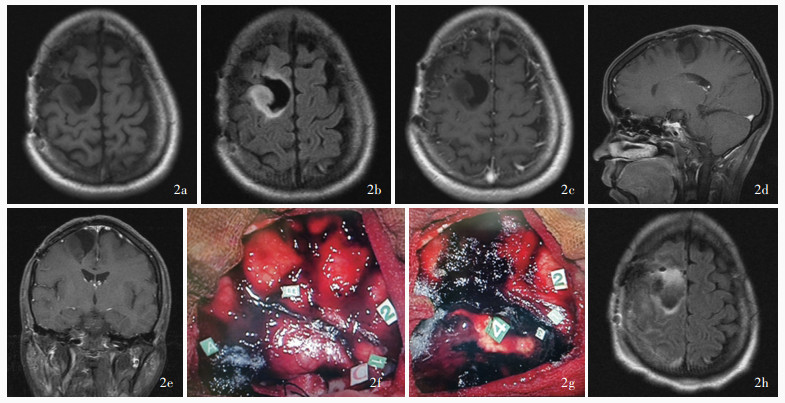

Yao S , Yang R , Du C , Jiang C , Wang Y , Peng C , Bai H . Maximal safe resection of diffuse lower grade gliomas primarily within central lobe using cortical/subcortical direct electrical stimulation under awake craniotomy. Front Oncol, 2023, 13: 1089139.

doi: 10.3389/fonc.2023.1089139

Zhan YF , Peng CQ , Li TD , Yao SJ , Yang RX , Zou YH , Bai HM . The role of direct electrical stimulation under awake craniotomy in resection of diffuse lower - grade glioma in the eloquent brain areas. Zhonghua Shen Jing Wai Ke Za Zhi, 2023, 39: 551- 555.

doi: 10.3760/cma.j.cn112050-20211112-00538

战俣飞, 彭冲奇, 李天栋, 姚书敬, 杨瑞鑫, 邹宇辉, 白红民. 术中唤醒直接电刺激技术在功能区较低级别弥漫性胶质瘤切除中的应用价值. 中华神经外科杂志, 2023, 39: 551- 555.

Ng S , Valdes PA , Moritz - Gasser S , Lemaitre AL , Duffau H , Herbet G . Intraoperative functional remapping unveils evolving patterns of cortical plasticity. Brain, 2023, 146: 3088- 3100.

doi: 10.1093/brain/awad116

Nassihi A , Duffau H . Functional and oncological outcomes following more than three consecutive surgical resections for multiple relapses of initially grade 2 IDH - mutated gliomas. Acta Neurochir (Wien), 2024, 166: 425.

doi: 10.1007/s00701-024-06321-6

Hamdan N , Duffau H . Extending the multistage surgical strategy for recurrent initially low - grade gliomas: functional and oncological outcomes in 31 consecutive patients who underwent a third resection under awake mapping. J Neurosurg, 2021, 136: 1035- 1044.

|